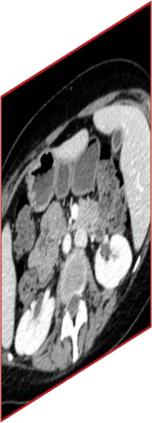

Due to the constraints of the imaging device and high cost in operation time, computer tomography (CT) scans are usually acquired with low intra-slice resolution. Improving the intra-slice resolution is beneficial to the disease diagnosis for both human experts and computer-aided systems. To this end, this paper builds a novel medical slice synthesis to increase the between-slice resolution. Considering that the ground-truth intermediate medical slices are always absent in clinical practice, we introduce the incremental cross-view mutual distillation strategy to accomplish this task in the self-supervised learning manner. Specifically, we model this problem from three different views: slice-wise interpolation from axial view and pixel-wise interpolation from coronal and sagittal views. Under this circumstance, the models learned from different views can distill valuable knowledge to guide the learning processes of each other. We can repeat this process to make the models synthesize intermediate slice data with increasing inter-slice resolution. To demonstrate the effectiveness of the proposed approach, we conduct comprehensive experiments on a large-scale CT dataset. Quantitative and qualitative comparison results show that our method outperforms state-of-the-art algorithms by clear margins.